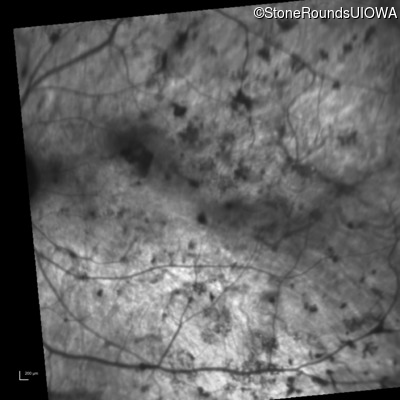

Infrared Fundus Photograph - Right - Light Perception

Exemplar